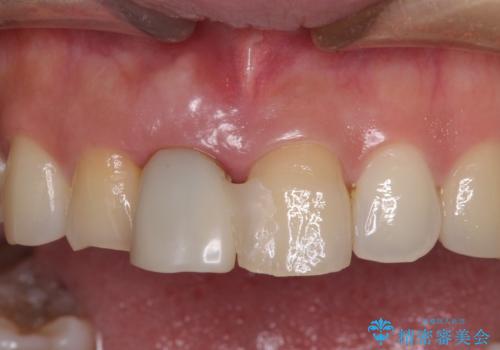

- 仮歯のまま前歯を放置しているとのことで来院された患者様です。

目視で確認できるほどしっかりとした破折が認められ、抜歯が必要と判断されました。

抜歯後は歯肉が痩せてしまうため、歯肉移植を行って歯肉の形態を改善した後、オールセラミックブリッジにて補綴することとしました。